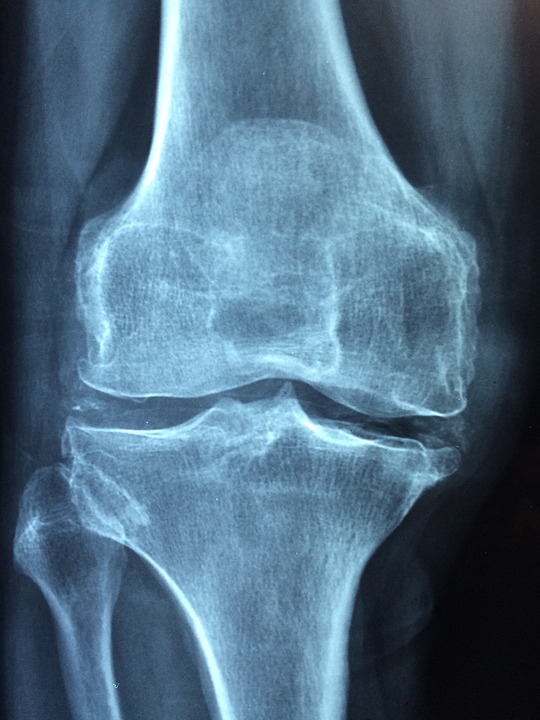

Arthritis Disability Claims

Arthritis afflicts the young and old; in Canada, there are over 8 million people affected by arthritis daily. According to The Public Health Agency of Canada, Arthritis is a chronic disease that is often incurable. An estimated 65% of those living with arthritis are women and close to 3/5 of those affected are younger than … Read more